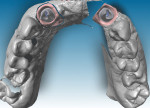

Four months later, following implant osseointegration and healing, a closed-tray impression was taken and models were prepared. The models were scanned in the Straumann CS2 in-lab scanner to facilitate the design of the final prosthesis (Figure 8). Straumann CARES® Titanium Abutments were designed in the CARES® Visual 8.0 Software for Nos. 7 and 10 (Figure 9).

Shortly thereafter, CARES Titanium Abutments were received at the laboratory from the Straumann Centralized Milling Facility in Arlington, Texas. The technician rescanned the model and final abutments to design the zerion® LT framework (Straumann) (Figure 10 through Figure 12).